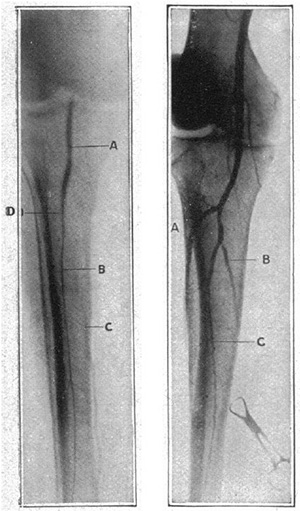

図3. ヨウ化ナトリウムによる下肢動脈造影.(左)前脛骨動脈閉塞,(右)後脛骨動脈,腓骨動脈の狭窄.

【要旨】ヨウ化ナトリウムによる下肢動脈造影を試みた.100%ヨウ化ナトリウムを調製,滅菌する.全麻下に,鼠径部で大腿動脈を外科的に露出し,血管鉗子で血流を遮断した動脈を穿刺して造影剤10ccを注入後,速やかにX線撮影を行なう.3症例が例示されており,それぞれ動脈閉塞による下腿潰瘍の症例,糖尿病による下肢動脈閉塞でその後下肢切断術を施行した症例,糖尿病性動脈閉塞と思われたが実は火傷による皮膚潰瘍であった症例である.下肢動脈造影は,四肢壊疽における切断術の適応,切断部位の決定に有用である.

【解説】ヨウ化ナトリウムによる下肢動脈造影の報告である.ヨウ化ナトリウムは,当時は梅毒の治療薬として血管内投与されており,1920年に逆行性尿路造影剤として使われ,また前年の1923年にはOsborneらが排泄性尿路造影に使用していた.前年の臭化ストロンチウムによるBerberichの末梢血管造影の論文は引用されておらず,おそらく独立に行なわれたものであろう.

駆血帯で静脈圧を高め,鉗子で閉塞して虚脱状態になった動脈に造影剤を注入している.つまり動脈内に造影剤をうっ滞させて撮影する方法で,短時間撮影ができなかった当時としては最良の方法と思われる.なかなか鮮明な造影像が得られているが,ヨウ化ナトリウムは100%溶液なので当然のことながら激しい血管痛があり,全身麻酔が必須であった.臨床的有用性への期待を述べ,暫定報とされているが続報は見当らない(Brooksはその後血管外科医として活躍したが,血管造影の仕事はこれだけである[3]).